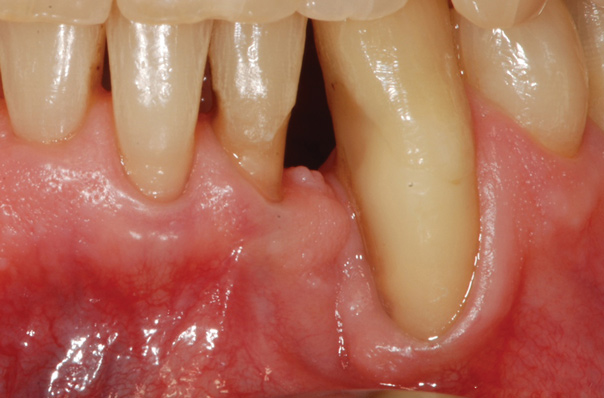

Fig 13. The scaffold was placed in the defect, where it remained for approximately 1 year. Fig 13: baseline; Fig 14: defect; Fig 15: scaffold matrix; Fig 16: scaffold placement; Fig 17: wound closure; Fig 18 through Fig 20: 2-month, 6-month, and 1-year postoperative, respectively. (Images reprinted with permission from Rasperini G, Pilipchuk SP, Flanagan CL, et al. J Dent Res. 2015;94[9 suppl]:153S-157S.)

Figure 13

Fig 14. The scaffold was placed in the defect, where it remained for approximately 1 year. Fig 13: baseline; Fig 14: defect; Fig 15: scaffold matrix; Fig 16: scaffold placement; Fig 17: wound closure; Fig 18 through Fig 20: 2-month, 6-month, and 1-year postoperative, respectively. (Images reprinted with permission from Rasperini G, Pilipchuk SP, Flanagan CL, et al. J Dent Res. 2015;94[9 suppl]:153S-157S.)

Figure 14

Fig 15. The scaffold was placed in the defect, where it remained for approximately 1 year. Fig 13: baseline; Fig 14: defect; Fig 15: scaffold matrix; Fig 16: scaffold placement; Fig 17: wound closure; Fig 18 through Fig 20: 2-month, 6-month, and 1-year postoperative, respectively. (Images reprinted with permission from Rasperini G, Pilipchuk SP, Flanagan CL, et al. J Dent Res. 2015;94[9 suppl]:153S-157S.)

Figure 15

Fig 16. The scaffold was placed in the defect, where it remained for approximately 1 year. Fig 13: baseline; Fig 14: defect; Fig 15: scaffold matrix; Fig 16: scaffold placement; Fig 17: wound closure; Fig 18 through Fig 20: 2-month, 6-month, and 1-year postoperative, respectively. (Images reprinted with permission from Rasperini G, Pilipchuk SP, Flanagan CL, et al. J Dent Res. 2015;94[9 suppl]:153S-157S.)

Figure 16

Fig 17. The scaffold was placed in the defect, where it remained for approximately 1 year. Fig 13: baseline; Fig 14: defect; Fig 15: scaffold matrix; Fig 16: scaffold placement; Fig 17: wound closure; Fig 18 through Fig 20: 2-month, 6-month, and 1-year postoperative, respectively. (Images reprinted with permission from Rasperini G, Pilipchuk SP, Flanagan CL, et al. J Dent Res. 2015;94[9 suppl]:153S-157S.)

Figure 17

Fig 18. The scaffold was placed in the defect, where it remained for approximately 1 year. Fig 13: baseline; Fig 14: defect; Fig 15: scaffold matrix; Fig 16: scaffold placement; Fig 17: wound closure; Fig 18 through Fig 20: 2-month, 6-month, and 1-year postoperative, respectively. (Images reprinted with permission from Rasperini G, Pilipchuk SP, Flanagan CL, et al. J Dent Res. 2015;94[9 suppl]:153S-157S.)

Figure 18

Fig 19. The scaffold was placed in the defect, where it remained for approximately 1 year. Fig 13: baseline; Fig 14: defect; Fig 15: scaffold matrix; Fig 16: scaffold placement; Fig 17: wound closure; Fig 18 through Fig 20: 2-month, 6-month, and 1-year postoperative, respectively. (Images reprinted with permission from Rasperini G, Pilipchuk SP, Flanagan CL, et al. J Dent Res. 2015;94[9 suppl]:153S-157S.)

Figure 19

Fig 20. The scaffold was placed in the defect, where it remained for approximately 1 year. Fig 13: baseline; Fig 14: defect; Fig 15: scaffold matrix; Fig 16: scaffold placement; Fig 17: wound closure; Fig 18 through Fig 20: 2-month, 6-month, and 1-year postoperative, respectively. (Images reprinted with permission from Rasperini G, Pilipchuk SP, Flanagan CL, et al. J Dent Res. 2015;94[9 suppl]:153S-157S.)

Figure 20